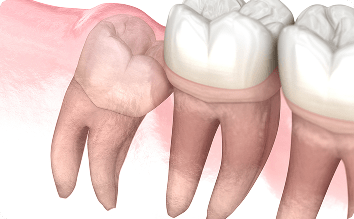

歯周病、むし歯

歯周囲炎と関連しますが、慢性的(定期的にずっと)に汚れが停滞していると、手前の歯にむし歯を作ったり歯周病を憎悪してしまう可能性があり、親知らずを抜歯したとしても手前の歯も大きくダメージを負う場合もあり、最悪の場合手前の歯の抜歯の可能性もあります。

これらの場合は、一般的に抜歯になる親知らずです。親知らずが不正歯列の原因に繋がることをご存じない方もいらっしゃると思いますが、親知らずが手前の歯にぶつかっている場合、手前の歯を押したりしますので、歯並びに悪影響を及ぼすことがあります。一度矯正しても親知らずが原因でまた歯並びが悪くなることもあります。